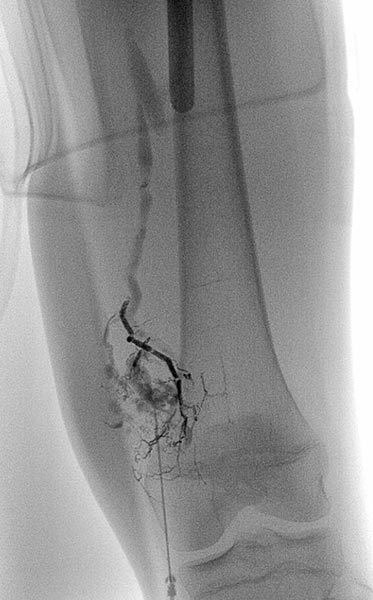

Über den Mikrokatheter wird jetzt selektiv mit Ethylen-Vinyl-Alkohol-Kopolymer embolisiert, das sich in den feinen Fisteln verteilt.

In der Röntgenübersichtsaufnahme nach Embolisation der Fisteln zeigt sich der selektive Ausguss der Fisteln mit dem röntgendichten Embolisat (Cast).

In der anschließenden Röntgen-Übersichtsangiographie sind die Fisteln vollständig verschlossen.